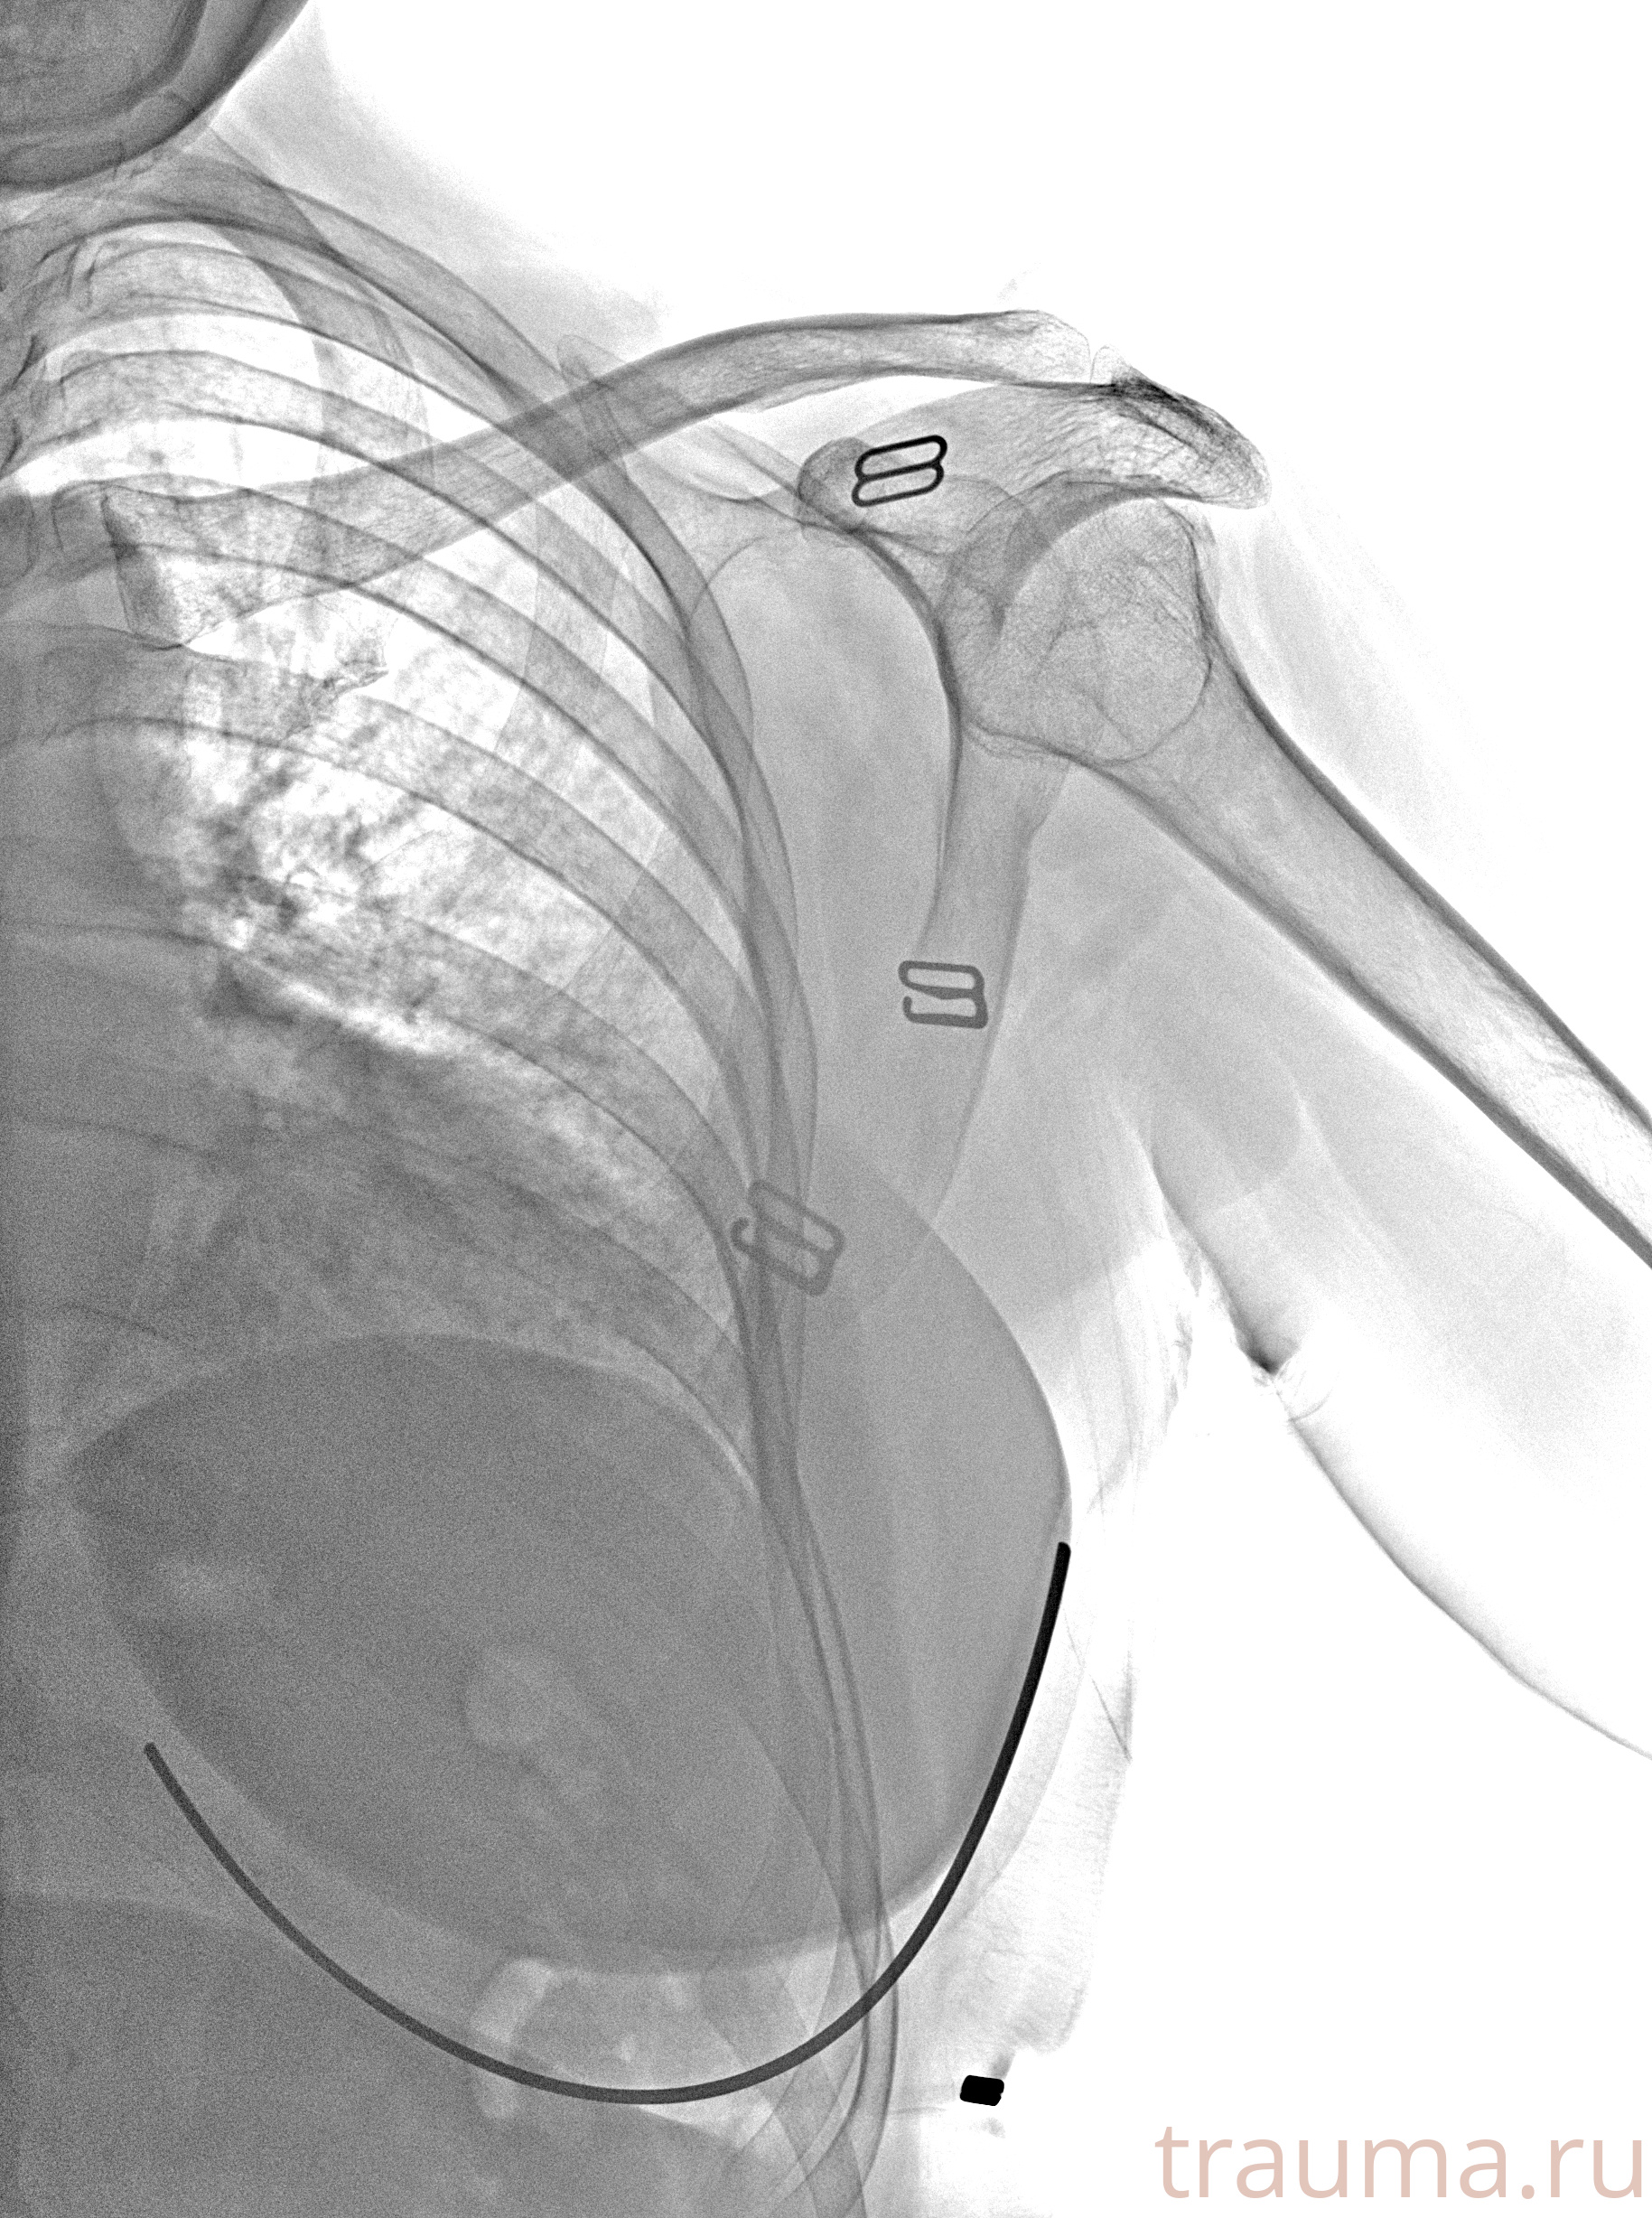

Рентгенограммы

Рентген на дому: по вашему адресу приезжает врач-рентгенолог, травматолог-ортопед с мобильным рентгеновским аппаратом, проводит диагностику травмы или заболевания, делает необходимые рентгенограммы, дает рекомендации по дальнейшему лечению. Получить качественные снимки в домашних условиях возможно благодаря уникальной методике, разработанной МосРентген Центром для института  Склифосовского